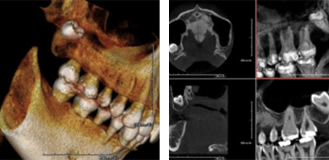

当医院では歯科用に特化した高性能なCTスキャンを導入致しました。

歯科用CTスキャナーは、従来の診断機器とはまったく異なる撮影方法により、お口全体の立体画像が撮影できます。

しかも、歯の中や骨の中まで立体的に見えるので、正確な治療計画を立てることができるのです。

通常のレントゲンでは2Dの画像しか撮影ができませんでしたがCTスキャンは立体的な3Dの撮影が可能です。

中でも「ファインキューブ」は従来の機器よりも放射線量が低く安全して診断を受けて頂けます。